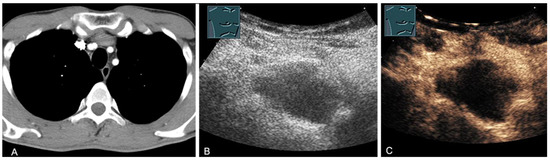

Figure 14.

A cystic mediastinal mass on CT (provided by Prof. Dr. Andreas H. Mahnken, Marburg, Germany) (A), B-mode US (B), and CEUS (C), surgically confirmed as a mediastinally located bronchogenic cyst.